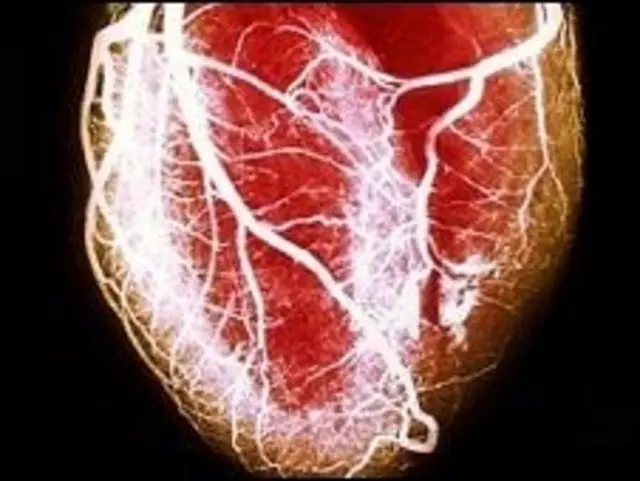

Si bien los especialistas dicen que no es posible morir de amor, quienes padecen este problema tienen cuatro veces más posibilidades de sufrir un infarto.

“Se pueden producir factores o sustancias que alteran la coagulación, y eso se asocia con el factor de riesgo cardiovascular”, dice en conversación con BBC Mundo.

El malestar que provoca una desilusión amorosa es real, e incluso existe el llamado Síndrome del Corazón Roto, un padecimiento que se presenta en pocos casos y cuyo nombre real es cardiopatía de Takotsubo.

Quienes lo padecen suelen tener todos los síntomas de un ataque cardíaco, pero en realidad es una ansiedad extrema causada por la depresión.